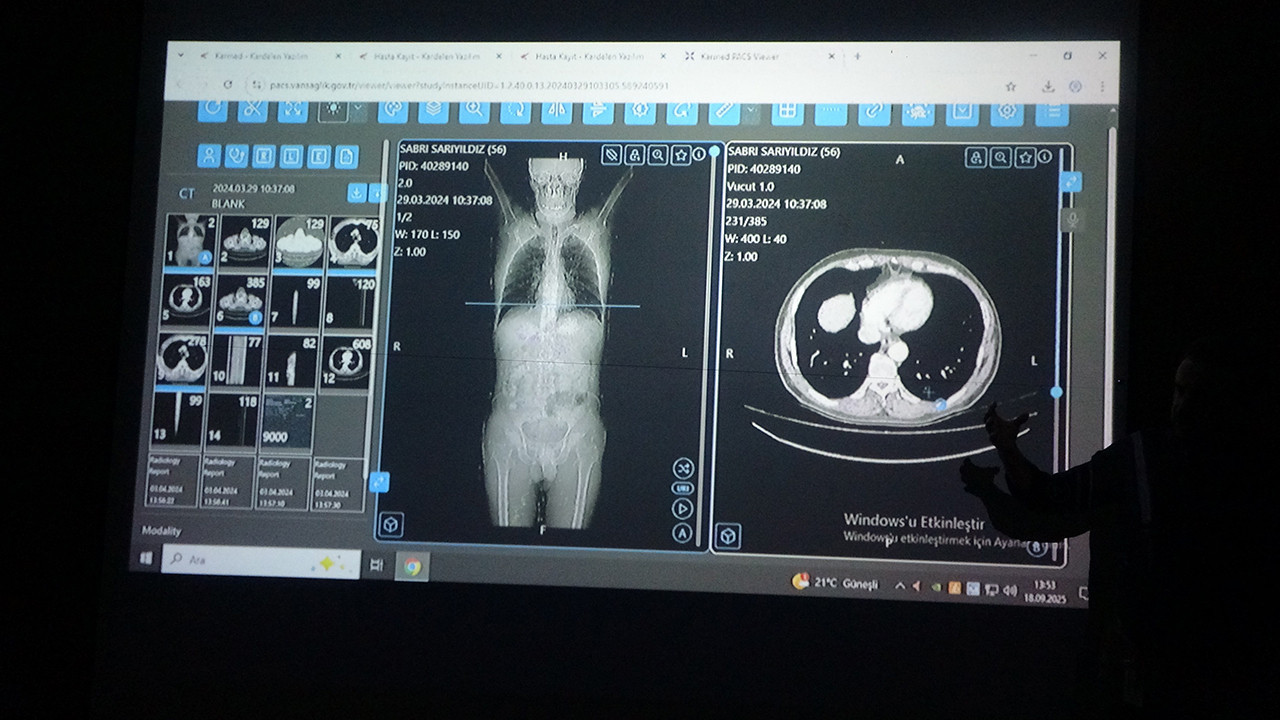

Van Bölge Eğitim ve Araştırma Hastanesi'nde kanser hastalarının tedavi süreçlerine yönelik dikkat çekici bir bilimsel çalışma yürütüldü. Prestijli uluslararası tıp dergisi Healthcare'de yayımlanan araştırmada; genel cerrahi, onkoloji, radyoloji, nükleer tıp, radyasyon onkolojisi ve patoloji uzmanlarının oluşturduğu konsey toplantılarına yapay zekâ destekli bir yazılım "katılımcı" olarak eklendi. Burada kanser tanısı konmuş 100 hasta hem hekimler hem de yapay zekâ tarafından değerlendirildi. Kararların yüzde 76 oranında örtüşmesi, konunun bilimsel çevrelerde de dikkatle takip edilmesine neden oldu. Çalışmada örnek vakalardan biri olarak, Erciş ilçesinde yaşayan 56 yaşındaki Sabri Sarıyıldız değerlendirildi. Yapay zekâ destekli yazılımın önerdiği tedavi planı, hekimlerin kararlarıyla birlikte uygulamaya konuldu. Sarıyıldız, izlenen bu yol sayesinde gerçekleştirilen başarılı cerrahi operasyon sonrası sağlığına kavuştu.

Konuya ilişkin konuşan Van Bölge Eğitim ve Araştırma Hastanesi Genel Cerrahi Uzmanı Prof. Dr. Sebahattin Çelik, yapay zekânın hekim kararlarıyla yüzde 76 oranında örtüştüğünü belirtti. Yapay zekânın sağlık alanında giderek daha yaygın kullanıldığı ifade eden Prof. Dr. Çelik, "Biz de Van Bölge Eğitim ve Araştırma Hastanesi olarak teknolojinin sunduğu en son imkânlardan faydalanarak hastalarımıza doğru tedaviyi ve doğru yaklaşımı sunmak için yapay zekâ algoritmalarını kullanıyoruz. Yakın zamanda prestijli bir dergide yayımlanan çalışmamızda, multidisipliner tümör konseylerinde yapay zekâ destekli bir yazılım kullandık. Bu konseylerde genel cerrahi, onkoloji, radyoloji, nükleer tıp, radyasyon onkolojisi ve patoloji gibi birçok farklı branştan uzman hekimler bir araya gelerek hastaların tedavi sürecine yönelik ortak kararlar almaktadır. Biz de bu konsey toplantılarında yapay zekâyı bir katılımcı olarak değerlendirdik. ChatGPT'nin son algoritmasını kullanarak kanser tanısı olan 100 hastamızı hem uzman hekimler hem de yapay zekâ değerlendirdi. Sonrasında alınan kararlar karşılaştırıldığında, yapay zekâ destekli verilen kararların hekimlerin kararlarıyla yaklaşık yüzde 76 oranında örtüştüğünü gördük. Bu oldukça çarpıcı ve önemli bir bulgudur. Çünkü bu durum, yapay zekâ algoritmalarının artık profesyonel bir meslek grubu olan doktorlara yakın düzeyde karar verebildiğini göstermektedir" dedi.